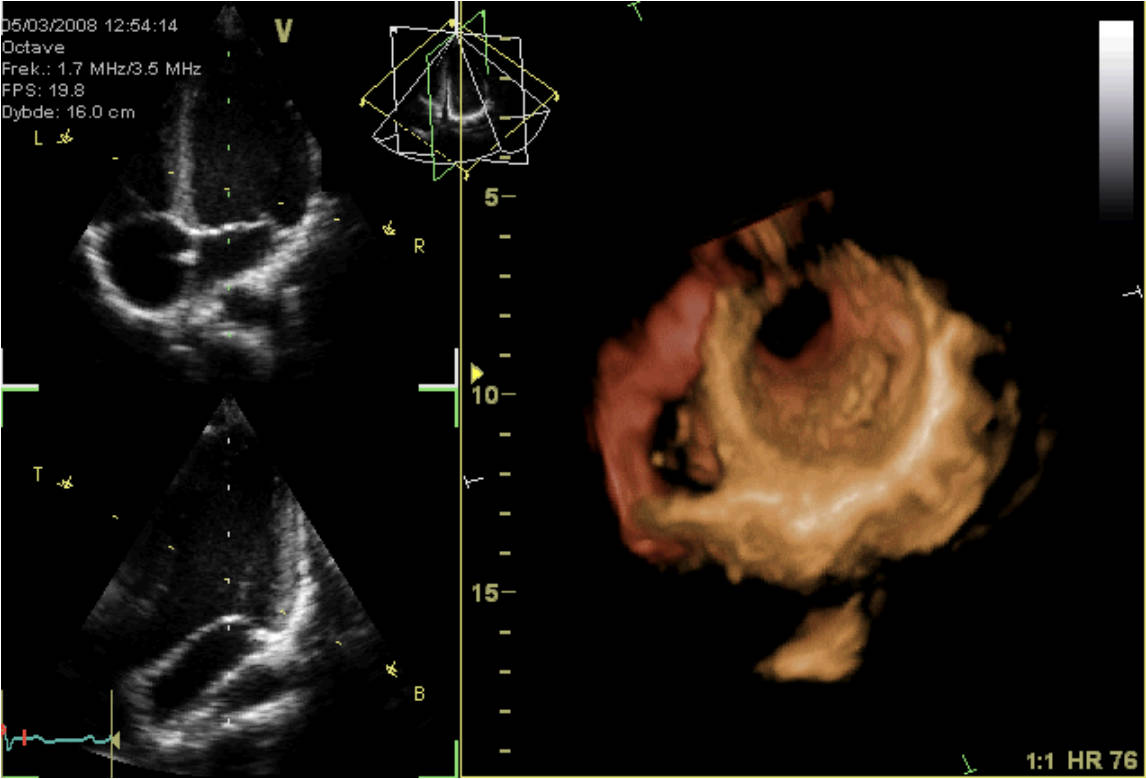

This image presents a sophisticated look at cardiac imaging, combining 2D echocardiogram views with a 3D reconstruction of the heart. Such advanced diagnostic tools are vital for non-invasively assessing heart structure and function, providing critical insights into cardiac health and disease. Understanding how to interpret these images is fundamental for cardiologists in diagnosing a wide range of cardiovascular conditions.

V Octave: This likely refers to the imaging modality or software used, indicating an advanced echocardiography system. “Octave” may signify its capability for detailed, high-resolution imaging.

Frek.: 1.7 MHZ/3.5 MHZ: This indicates the transducer frequency used for the ultrasound examination. Lower frequencies (e.g., 1.7 MHz) typically penetrate deeper, while higher frequencies (e.g., 3.5 MHz) offer better resolution for superficial structures.

FPS: 19.8: Stands for Frames Per Second, indicating the rate at which the ultrasound images are captured and displayed. A higher FPS allows for better visualization of rapid cardiac motion.

Dybde: 16.0 cm: This refers to the depth setting of the ultrasound scan, indicating that the machine is imaging structures up to 16.0 centimeters from the transducer. This parameter is adjusted based on the patient’s anatomy and the structures being examined.

HR 76: This is the heart rate, measured at 76 beats per minute. A normal heart rate is a key indicator of cardiac rhythm and overall cardiovascular health.

2D Echocardiogram Views (Upper and Middle Panels): These grayscale images represent standard two-dimensional ultrasound cross-sections of the heart. They allow for real-time visualization of cardiac chambers, valves, and wall motion, showing the heart’s pumping action.

3D Reconstruction (Right Panel and Lower Left Panel): This vividly colored image showcases a three-dimensional model of the heart, constructed from multiple 2D ultrasound slices. It provides a comprehensive spatial understanding of the heart’s external and internal structures, including the great vessels and chambers.

The combination of 2D and 3D echocardiography provides a holistic view of cardiac health. The 2D views offer dynamic, cross-sectional insights into myocardial contractility, valve motion, and the presence of any abnormal fluid collections around the heart. The 3D reconstruction, on the other hand, allows for a comprehensive spatial understanding of complex cardiac anatomy, which is particularly useful for assessing congenital heart defects or guiding complex procedures. For example, assessing the heart rate (HR 76 bpm in this image) alongside visual data gives a complete picture of cardiac performance.